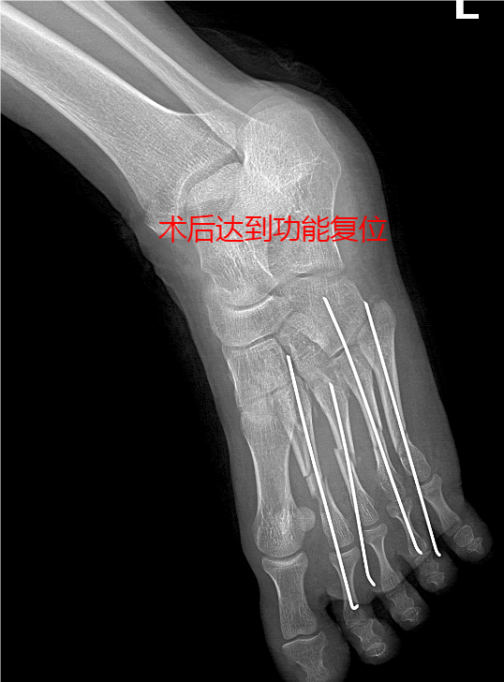

病案简要:患者因“砖块砸伤左足,疼痛、流血、活动受限1小时余。”入院。完善左足DR示:1、左足第3-5跖骨中段骨折。2、左足第2跖骨粉碎性骨折。以“左足开放性损伤伴多发骨折”收入我科 。门诊处查看创口:左足见约10cm不规则创口,深达筋膜层,创面内异物残留,左足肿胀明显,皮肤剥脱,触压痛,活动稍受限,远端足趾肤色正常,感觉稍差。初步诊断:1、左足部开放性损伤伴骨折(左足开放性2、3、4、5跖骨骨折);2、左足皮肤部分剥脱;3、左足软组织损伤并异物残留。入院后完善相关检查后行急诊手术,术后修整皮瓣,予VSD负压吸引,两个疗程后打开VSD见新生皮肤生长,剥脱皮肤成活80%以上,术口无任何感染。